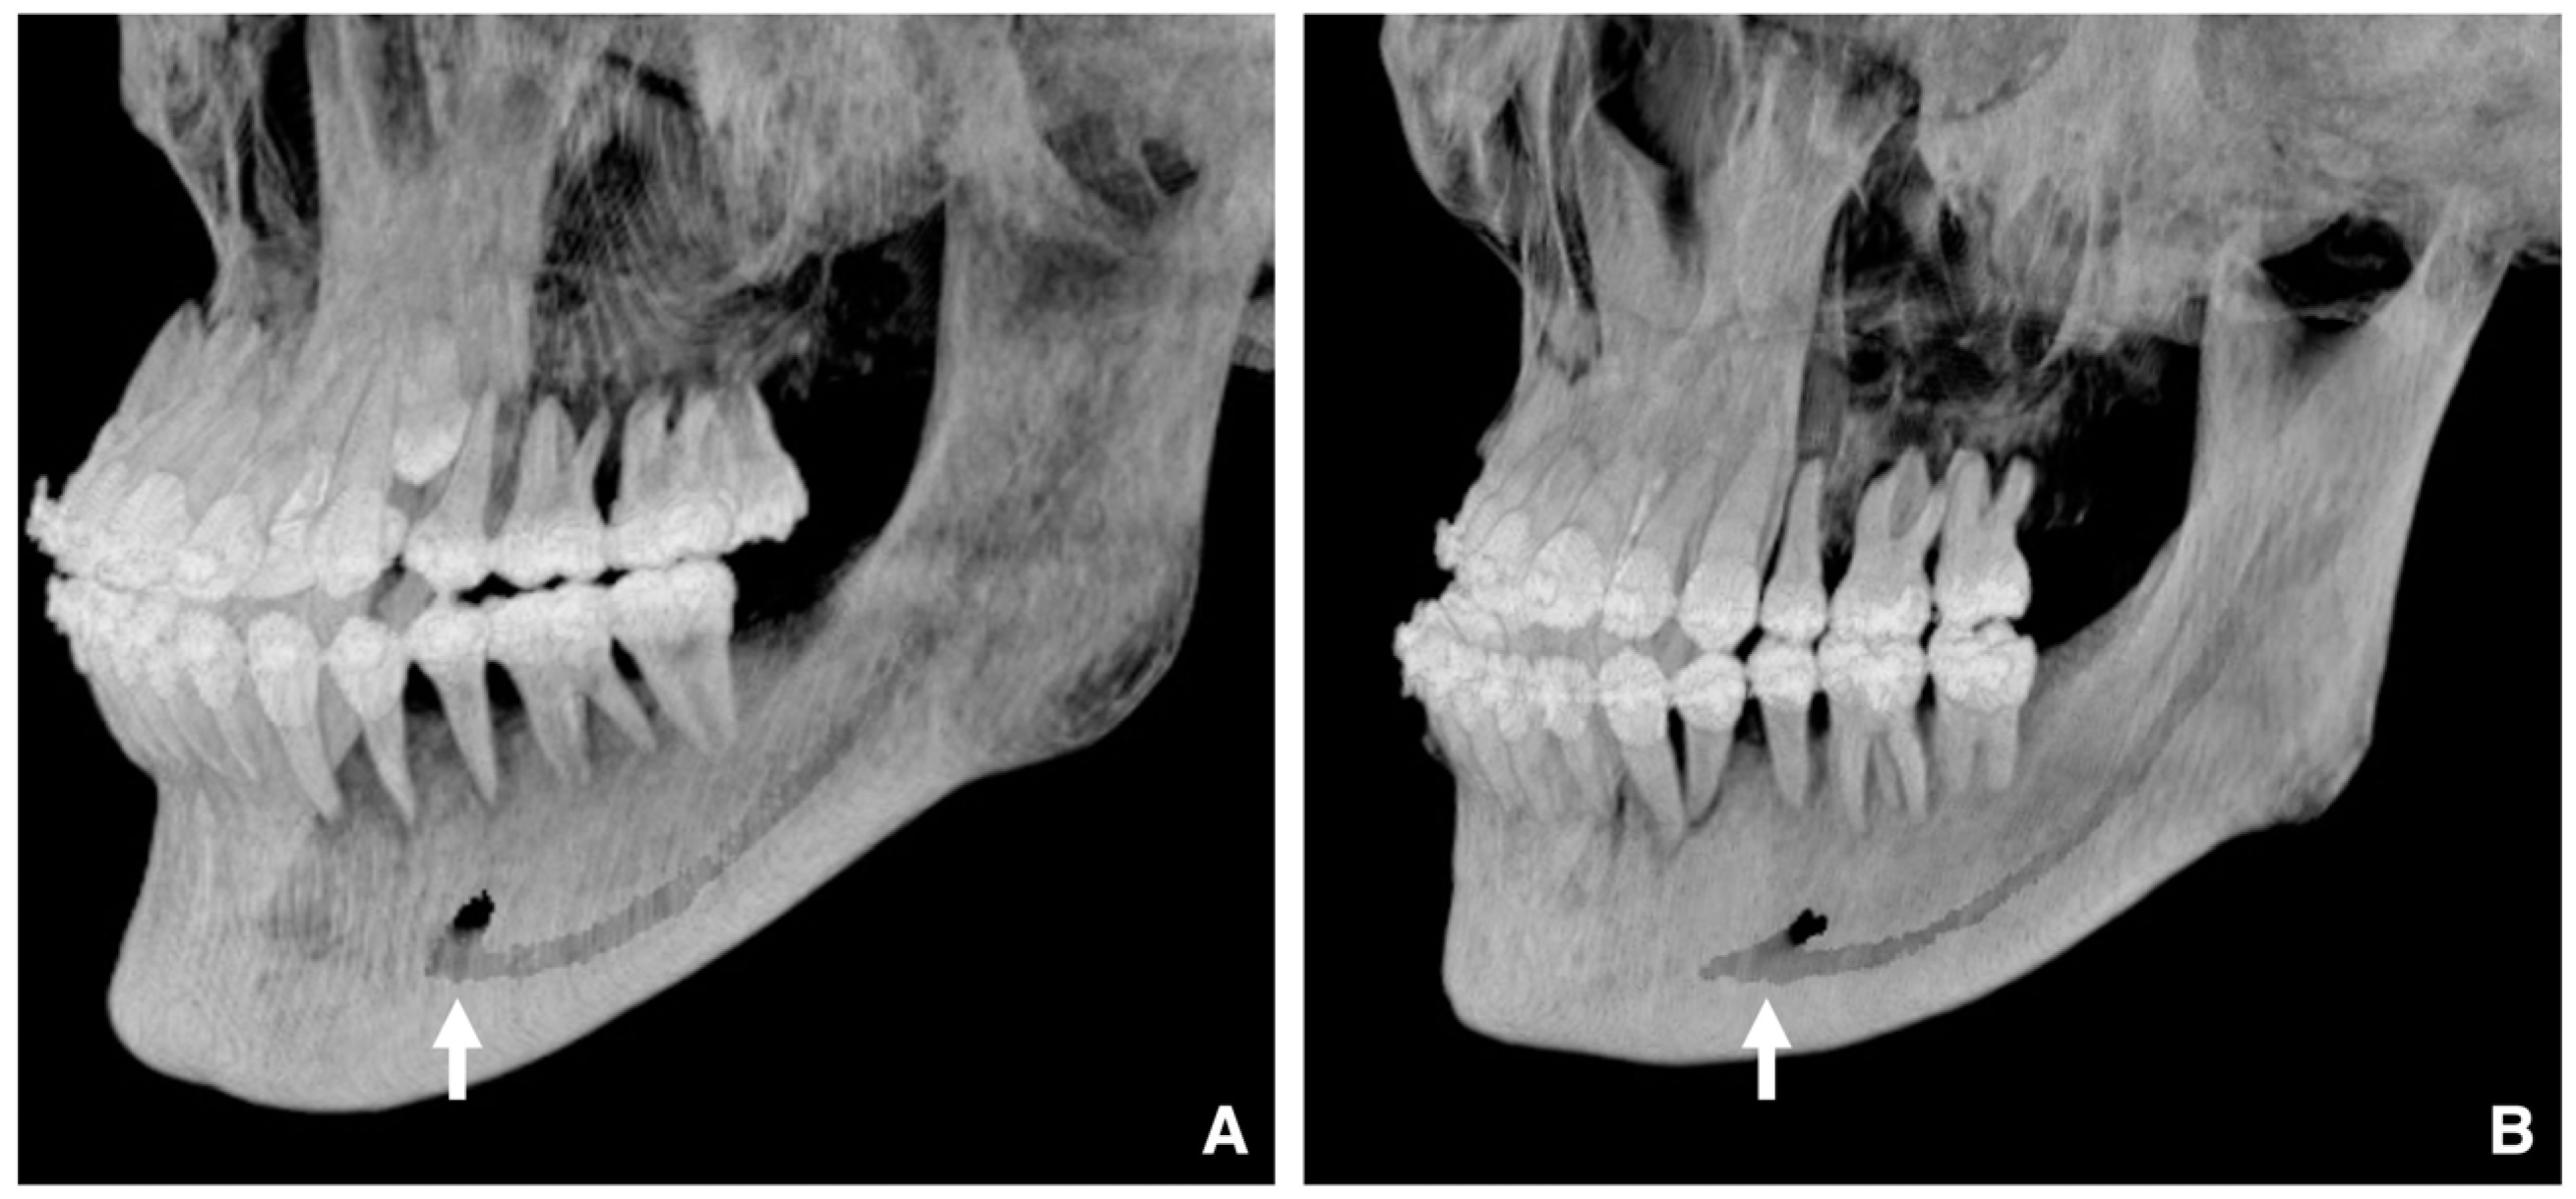

| Setting the osteotomy line 1. Evaluation of the position of the mandibular canal and surrounding bone quality Presence or absence of mandibular canal bifurcation and course of resection site Distance from the buccal wall of the mandibular canal to the buccal cortical bone margin Bone quality around the mandibular canal (CT number) 2. Distance from the mandibular notch to the lingula Whether it is 14 mm or more 3. Morphology of the mandible and variation in cortical bone thickness Cortical bone thickness in the medial osteotomy area and lateral osteotomy area Enhanced safety through improved visibility 1. Medial curvature of the mandibular ramus Mandibular ramus is straight or strong curvature 2. Course of small blood vessels along the bone surface Depression of the buccal-lingual cortical bone from the mandibular fossa to the mandibular ramus region, trabecular bone defect Improved success rates through enhanced postoperative bone integration 1. Degree of interference between bone segments The presence or absence of interference between the proximal and distal bone segments formed during virtual mandibular deformity surgery |

| Enhanced safety through improved visibility 1. Course of the submental artery and its branches Identification of the submandibular gland and its medial aspect 2. Course of the sublingual artery and the mental nerve Identification of the mentalis muscle, hyoglossus muscle, and anterior belly of the digastric muscle and their medial aspects (Observed within the fatty tissue beneath the chin) 3. Course of small blood vessels along the bone surface Degree of looping at the mentum foramen during opening, course of the incisive branch Setting the osteotomy line 1. Position of the mental foramen and course of the incisive branch Record the position of each root for each lower tooth 2. Position of the mandibular anterior tooth roots Record the thickness of the cortical bone using the mandibular teeth as a reference point 3. Variation in cortical bone thickness in the anterior mandible Depression of the cortical bone in the mandibular anterior region, trabecular bone defect |

- Kuroyanagi, N.; Miyachi, H.; Kanazawa, T.; Kamiya, N.; Nagao, T.; Shimozato, K. Morphologic features of the mandibular ramus associated with increased surgical time and blood loss in sagittal split-ramus osteotomy. J. Oral Maxillofac. Surg. 2013, 7, e31–e41. [Google Scholar] [CrossRef]